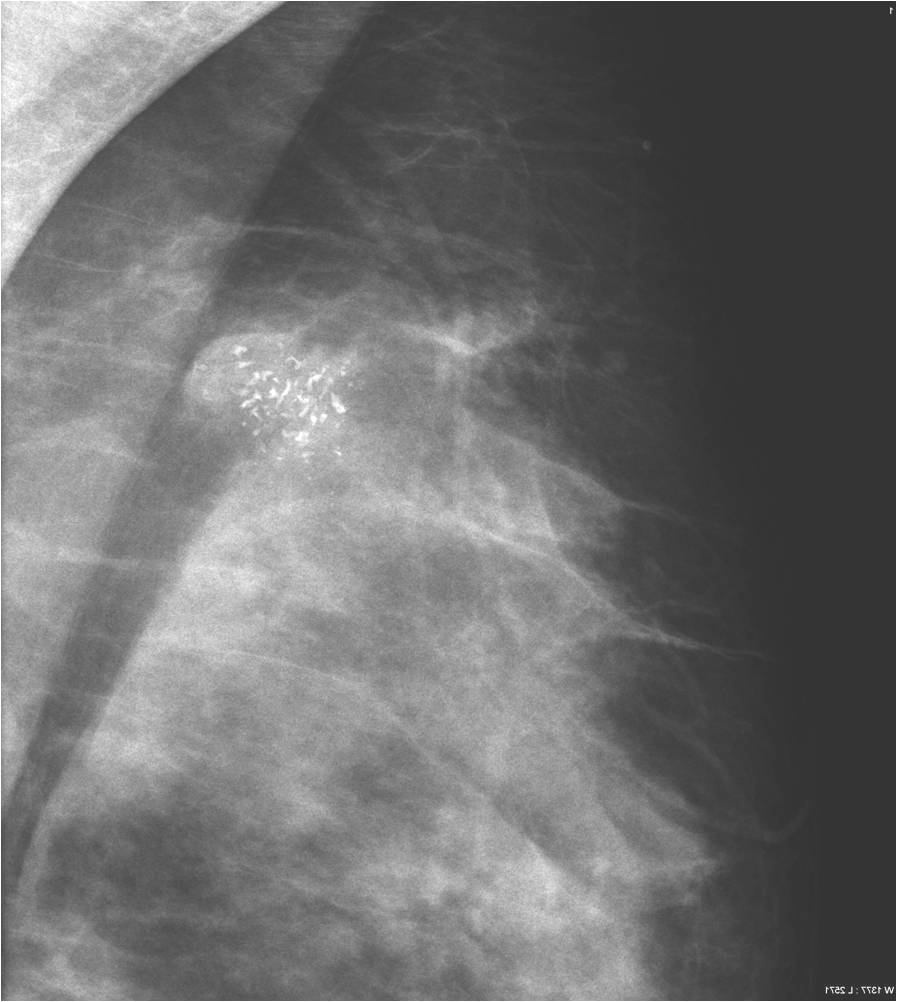

Pathologic lesions in the breast appear as various shapes and densities of soft tissues or calcificications or as the combinations of these two on mammography (Picture 16.). At many times only a few scattered, ill-defined, pleiomorphic microcalcifications indicate the presence of a pathologic lesion.

Calcifications appearing in the breast:

Calcifications are encountered in the breast quite often. Most of them accompany benign process (Picture 21.) and only a smaller percentage actually indicates malignancy. These malignant signs are basically always micro-calcifications. They are ill-shaped, with various pleomorphism (Pictures 23.,24.) and they are usually show a clustered arrangement. Their number is irrelevant to the grade of malignancy. Their analysis with mammography is often hard, but targeted and magnified images can help in it. In most the cases these lesion can’t be identified with ultrasound, so stereotaxy core biopsy is needed.